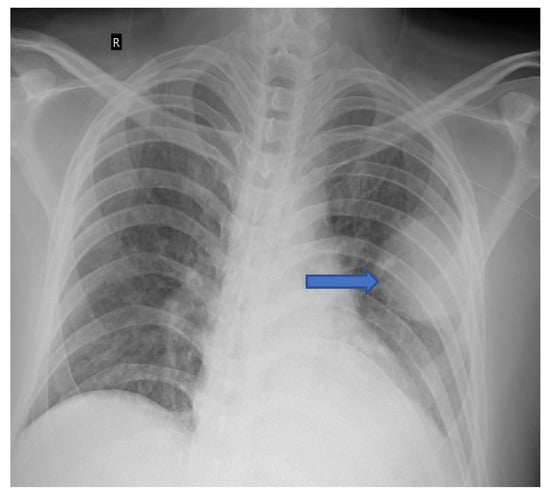

5.1. Role of Diagnostic Imaging

Diagnostic imaging is vital for early detection of invasive mucormycosis in patients with clinical suspicion. Certain distinguishing features of the lung parenchyma on a CT scan of the chest in patients with PM include multiple pulmonary nodules, often pleural-based, presence of lung cavitations and effusions (Figure 1, Figure 2, Figure 3 and Figure 4) [23]. The ‘reverse halo sign’ (central ground glass opacity surrounded by dense consolidation) is highly appreciated, mainly in neutropenic leukemic hosts. In a recent systematic review of CT findings in 16 patients with proven CAPM, consolidation and cavitation were seen in 11 (69%) patients, pleural effusion in 7 (47%), pneumothorax and nodules in 3 (19%) and ‘reverse halo sign’ and pulmonary embolism was seen in 2 (13%) patients [24]. Previously, Nam et al. reported that in hematologic patients, while consolidation and nodules are seen earlier in the disease process, central necrosis, cavitation and the air crescent sign are late findings [25]. This would suggest that CAPM is either under-diagnosed due to lack of differentiation from other fungal, including aspergillosis or bacterial pneumonias, or is diagnosed much later in the illness.

Figure 1. Chest radiograph (AP view) of patient showing round opacity in left lung (blue arrow).